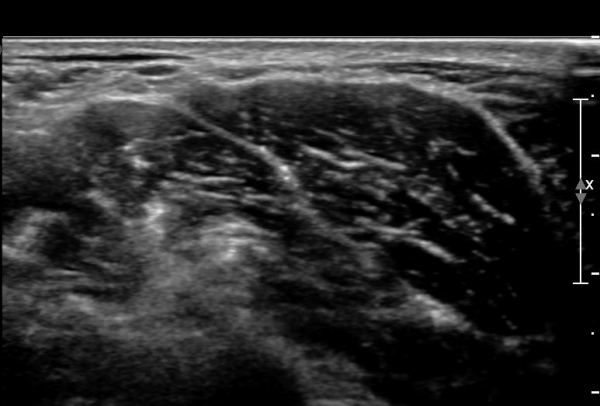

ÃÊÀ½ÆÄ ¼Ò°ß : ¸ñ ¿ÜÃø Á߾ӺΠȾ´Ü¸é°Ë»ç»ó Èä¼âÀ¯µ¹±Ù ÈÄ¹Ý °ß°©°Å±Ù Ç¥Ãþ¿¡¼­ ôÃߺνŰæÀÌ Àú¿¡ÄÚ

¿øÇü ±¸Á¶¹°·Î °üÂûµÈ´Ù(»çÁø 1, 2, 3).